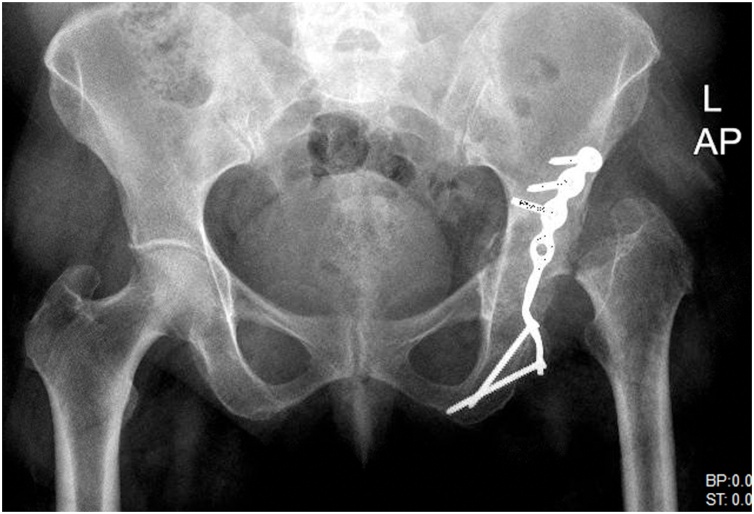

Infection laboratory workup, including the hip joint aspiration and triphasic bone scan, were negative. Left hip plain radiographs and CT scan demonstrated destruction and resorption of the left femoral head (Fig. 2).

Fig. 2.

Case 1; Anteroposterior and lateral pelvis radiograph displaying left femoral head resorption following an intra-articular corticosteroid injection.